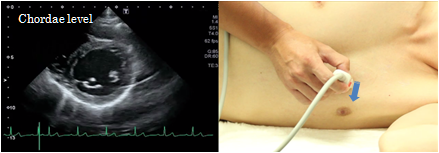

Chordae level

At the chordae level of the short axis view of the left ventricle, the chordae extending from the cusps of the mitral valve can be visualized. At this time, the left ventricle should be visualized so that it looks like a perfect circle. This view is used for evaluation of wall motion abnormality and measurement of the left ventricle by the M-mode method.